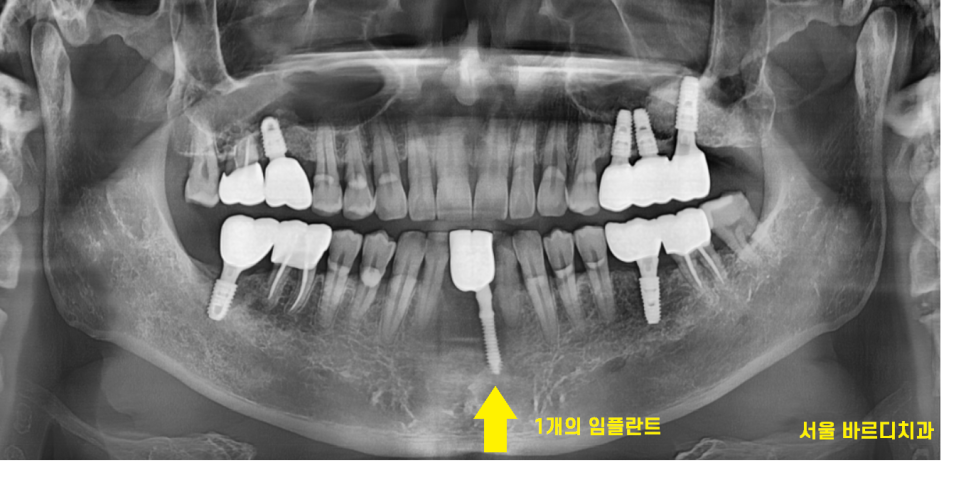

24.02.19

둔촌동 치과에서 2개가 빠졌지만

1개의 임플란트로 2개 효과를 ㅎㅎ

그렇지만 엑스레이로 보면?

1개의 임플란트죠~?